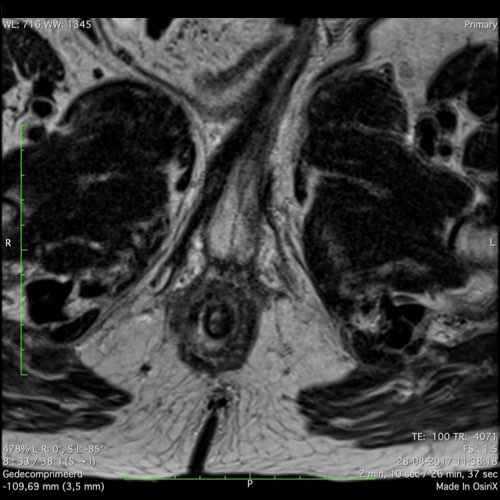

Hình ảnh

Các hình ảnh được cung cấp cho thấy ung thư biểu mô tế bào nhẫn với tình trạng dày lan tỏa thành trực tràng, hình ảnh bia bắn điển hình, và sự xâm lấn mỡ mạc treo trực tràng.